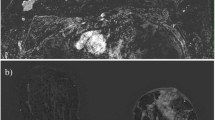

Texture analysis was performed using MaZda version 4.7 [32] on baseline and interim T2-weighted images. Post-contrast subtracted images from both examinations of each patient were considered side-by-side to identify maximum lesion diameter on each; subsequently these slices were matched to the appropriate slice on the T2 acquisition for region of interest (ROI) positioning on comparable slices (see Fig. 2). All image analysis was performed blinded to patient outcome, clinical and pathology information.

Region of interest (ROIs) (red) drawn for texture analysis on two patients, with slices matched between baseline (left column) and interim (right column) examinations. Insert images highlight lesion locations without ROI overlay. Image (a) and (b) are from slice-matched T2-weighted images from a woman who had a RCB-III at final pathology, while (c) and (d) are from slice-matched images in a patient that ultimately achieved a pCR at end of treatment. Images (e) and (f) highlight the importance of correlation with the subtracted dynamic contrast-enhanced imaging (DCE) images, particularly in the case of non-mass enhancement, as shown

T2-weighted images were magnified to visualise the tumour border and an ROI drawn around the entire tumour on the imaging slice demonstrating maximum lesion diameter, with no marker clip present. Histograms were visualised to ensure no fat was erroneously present within the ROI (see Fig. 2). A 10 × 10 pixel ROI was placed in healthy, normal contralateral breast parenchyma to exclude systematic inter-scan differences (as shown in Fig. 2(c,d)). These were placed in comparable regions of breast parenchyma at baseline and interim to ensure consistency and care was taken to exclude presence of vessels within the ROI. Data was rescaled to 6 bits/pixel and the image histogram normalized to within 3 standard deviations of the mean to minimise brightness and contrast variations. Entropy features, representing heterogeneity, were derived from the grey-level co-occurrence matrix [33], as these are reported in the literature as most appropriate for cancer imaging [29]. Inter-pixel distances of n = 2 and n = 5 were calculated to depict fine and coarse texture. Raw feature values were exported for statistical analysis.